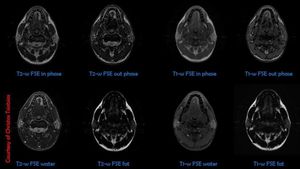

Neck MR imaging using IDEAL/Dixon technique. IDEAL (Iterative Decomposition of water and fat with Echo Asymmetry and Least-squares estimation) technique combines 3 echoes (acquired at different TE's) and better algorithms to create water-only (fat-suppressed) and fat-only images. Excellent uniformity of fat suppression is seen in both T1-w and T2-w IDEAL imaging, due to its inherent insensitivity to B0 and B1 inhomogeneities.